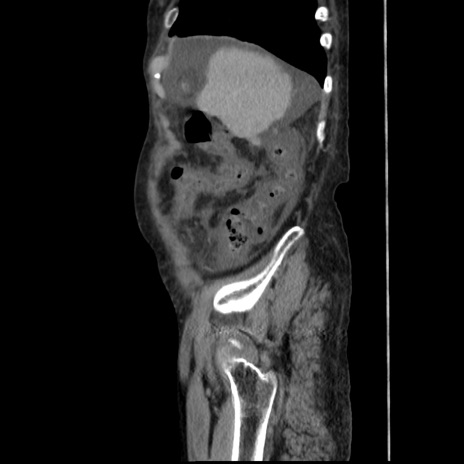

症例31(矢状断像)

【症例】80歳代 女性

【主訴】腹部膨満感

【現病歴】他院にて肝硬変にてフォロー中。1週間前から便秘、腹部膨満感、臍部腫瘤あり受診となる。

【既往歴】肝硬変

【身体所見】腹部膨隆あり、皮膚変化なし、疼痛なし。

【データ】WBC 4600、CRP 0.25